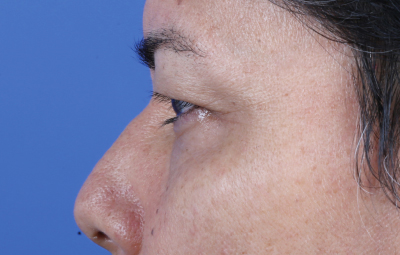

Es una ayuda diagnóstica complementaria que se utiliza para capturar imágenes de cualquier parte del cuerpo, aplicando técnicas que permitan obtener fotografías proporcionales, detalladas y nítidas; empleadas para medir, trazar, predeterminar y planear un proceso quirúrgico.

Es utilizada para crear imágenes del cuerpo humano, o partes de él, con propósitos clínicos que buscan revelar, diagnosticar y planear un tratamiento médico.